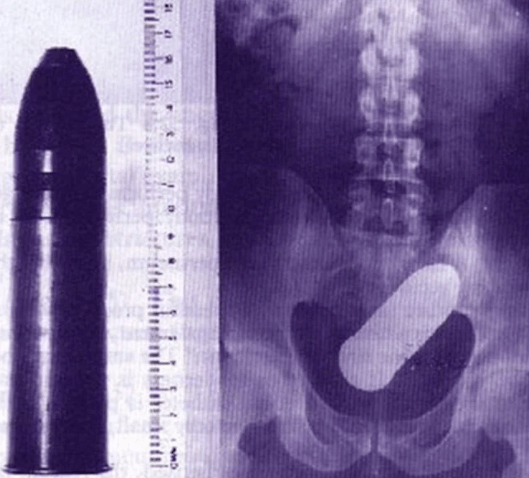

12月16日,一名88歲的老人被送到位於法國土倫市的Sainte Musse醫院就診,説是直腸內卡入異物,需要趕緊取出。

但是醫生檢查後發現,老人直腸內竟然有一枚炮彈!嚇得醫院趕緊報警,同時疏散了醫院的病人和工作人員,因為誰也不知道這枚炮彈的情況,會不會爆炸!

警方和拆彈專家很快來到了醫院,發現這枚炮彈是真的,而且是一款一戰時期法國軍隊曾經使用過的炮彈,但是因為年代久遠,爆炸可能性不大。

醫生在拆彈專家的配合下,小心翼翼地為老人做了手術,將炮彈取出,看着這枚長達20cm的炮彈,所有醫生都震驚不已,這到底是怎麼出現在直腸裏的?有醫生坦言:“我們之前取出過蘋果,芒果,甚至是一罐剃鬚泡沫,但我是從沒看過有人往自己肛門塞入一枚一戰炮彈。”